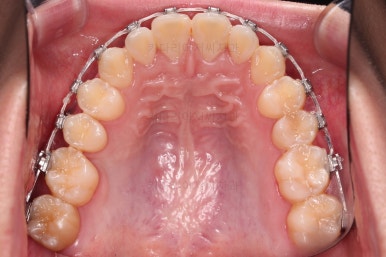

중앙선과 교합을 고려해서 좀 더 밀고 당기기를 해주고 마무리를 하게 됩니다.

우측의 결손치아보다 뒤쪽에 있는 치아는 크기나 모양이 원래의 큰 어금니보다 작고 다르게 생겨서 100% 이상적인 교합을 얻기는 한계가 있었어요.

하지만 임플란트 없이 충분히 가능할 수 있게끔 해주어서 환자분도 매우 만족하는 치료가 되었어요.

뿌리도 남아있었고 골 결손도 심했던터라 뒤쪽 치아들이 잘 움직일 것을 고지해 드렸었지만 다행히 거의 문제 없이 치아가 잘 움직였고요.

대신 해당 치아는 뼈가 약하다는 걸 환자분도 인지하시고 관리를 잘해야되는 부분입니다.

이제 전후 비교를 해볼게요.

1년 7개월 만에 매우 고난이도의 치료를 임플란트 없이 사랑니까지 당겨와서 사용한 만족스러운 치료였습니다.